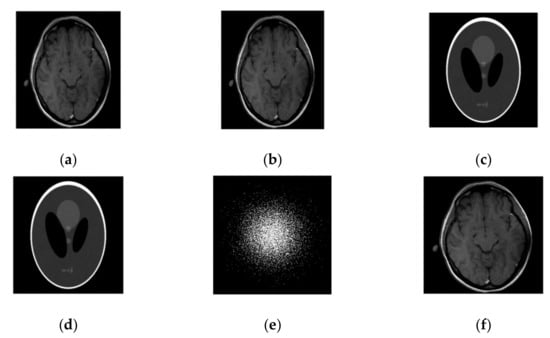

We first compared our proposed method with the DLMRI in a noiseless case. Figure 1 shows the performance of algorithm on brain and phantom image in noiseless scenario. Algorithm performance on a phantom and a brain image is evaluated using a 2D variable density random sampling of k-space. The dictionary learning algorithm (SiFo) reconstructed both the images free from artifacts and the aliasing effect. The results were achieved by running our algorithm for 15 iterations. The reconstruction with SiFo algorithm is clearer and sharper than with DLMRI.

Figure 1.

Algorithm performance in a noiseless case. (a) PSNR vs. iterations with comparison to DLMRI for a brain image; (b) HFEN vs. iterations with comparison to DLMRI for a brain image; (c) PSNR vs. iterations with comparison to DLMRI for a phantom image; (d) HFEN vs. iterations with comparison to DLMRI for a phantom image.

The SiFo performs better to capture the image of brain and phantom with fast convergence than DLMRI. This can be easily observed from Figure 1 and Figure 2, where our method showed better edges and sufficient features of reconstruction images.

Figure 2.

Images recovery for noiseless case. (a) Recovered MR image of brain by SiFo; (b) Recovered MR image of brain by DLMRI; (c) Recovered MR image of phantom by SiFo; (d) Recovered MR image of phantom by DLMRI; (e) Reconstruction brain image with zero filling; (f) Reference MR image for brain; (g) k-space sampling mask with 10 fold.